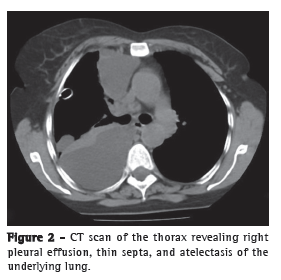

A chest X-ray demonstrated significant right-sided pleural effusion (Figure 1), and a CT scan of the chest revealed right pleural effusion, thin septa, and atelectasis of the underlying lung (Figure 2). Serum levels of urea and creatinine were 132 mg/dL and 3.9 mg/dL, respectively. Because the respiratory distress developed suddenly and soon after percutaneous nephrolithotomy, urinothorax was suspected. The diagnosis was confirmed after thoracocentesis, which yielded approximately 1,100 mL of pleural fluid, with a ratio between the creatinine content in pleural fluid and that in serum of 1.78 (normal, < 1). A 28 Fr chest tube was inserted into the right fifth intercostal space in order to drain the effusion.